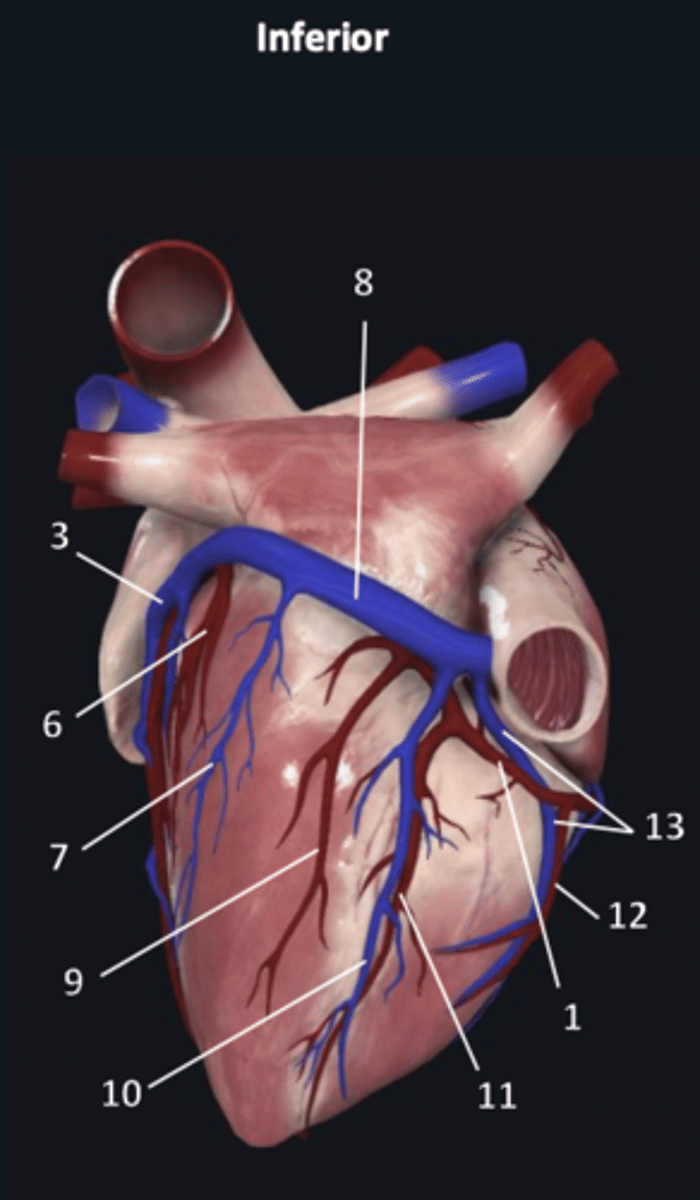

right coronary artery

1

anterior interventricular artery

2 (red)

great cardiac vein

3 (blue)

anterior interventricular artery

2 (red)

great cardiac vein

3 (blue)

left marginal artery

4

left marginal vein

5

posterior left ventricular artery

6

posterior vein of left ventricle

7

coronary sinus

8

right coronary artery

1 (red)

great cardiac vein

3

posterior left ventricular artery

6

posterior vein of left ventricle

7

coronary sinus

8

right posterolateral artery

9

middle cardiac vein

10

posterior interventricular artery

11

right marginal artery

12

small cardiac vein

13